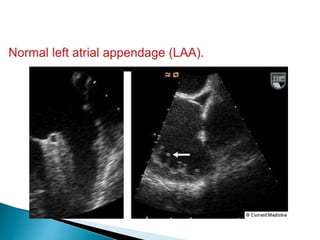

 Purpose of the left atrial appendage (LAA) is not fully understood.

 LAA acts as a capacitance chamber allowing sudden changes in LA

volume to be accommodated without marked increases in left atrial

pressure (LAP)

 The LAA acts as a cul-de- sac with a high incidence of thrombus

especially in the presence of atrial fibrillation (AF).

 The orifice of the neck of the appendage curves around the lateral

aspect of the LA between the left upper pulmonary vein (LUPV)

(posteriorly) and the junction of the LA and pulmonary trunk

(anteriorly).